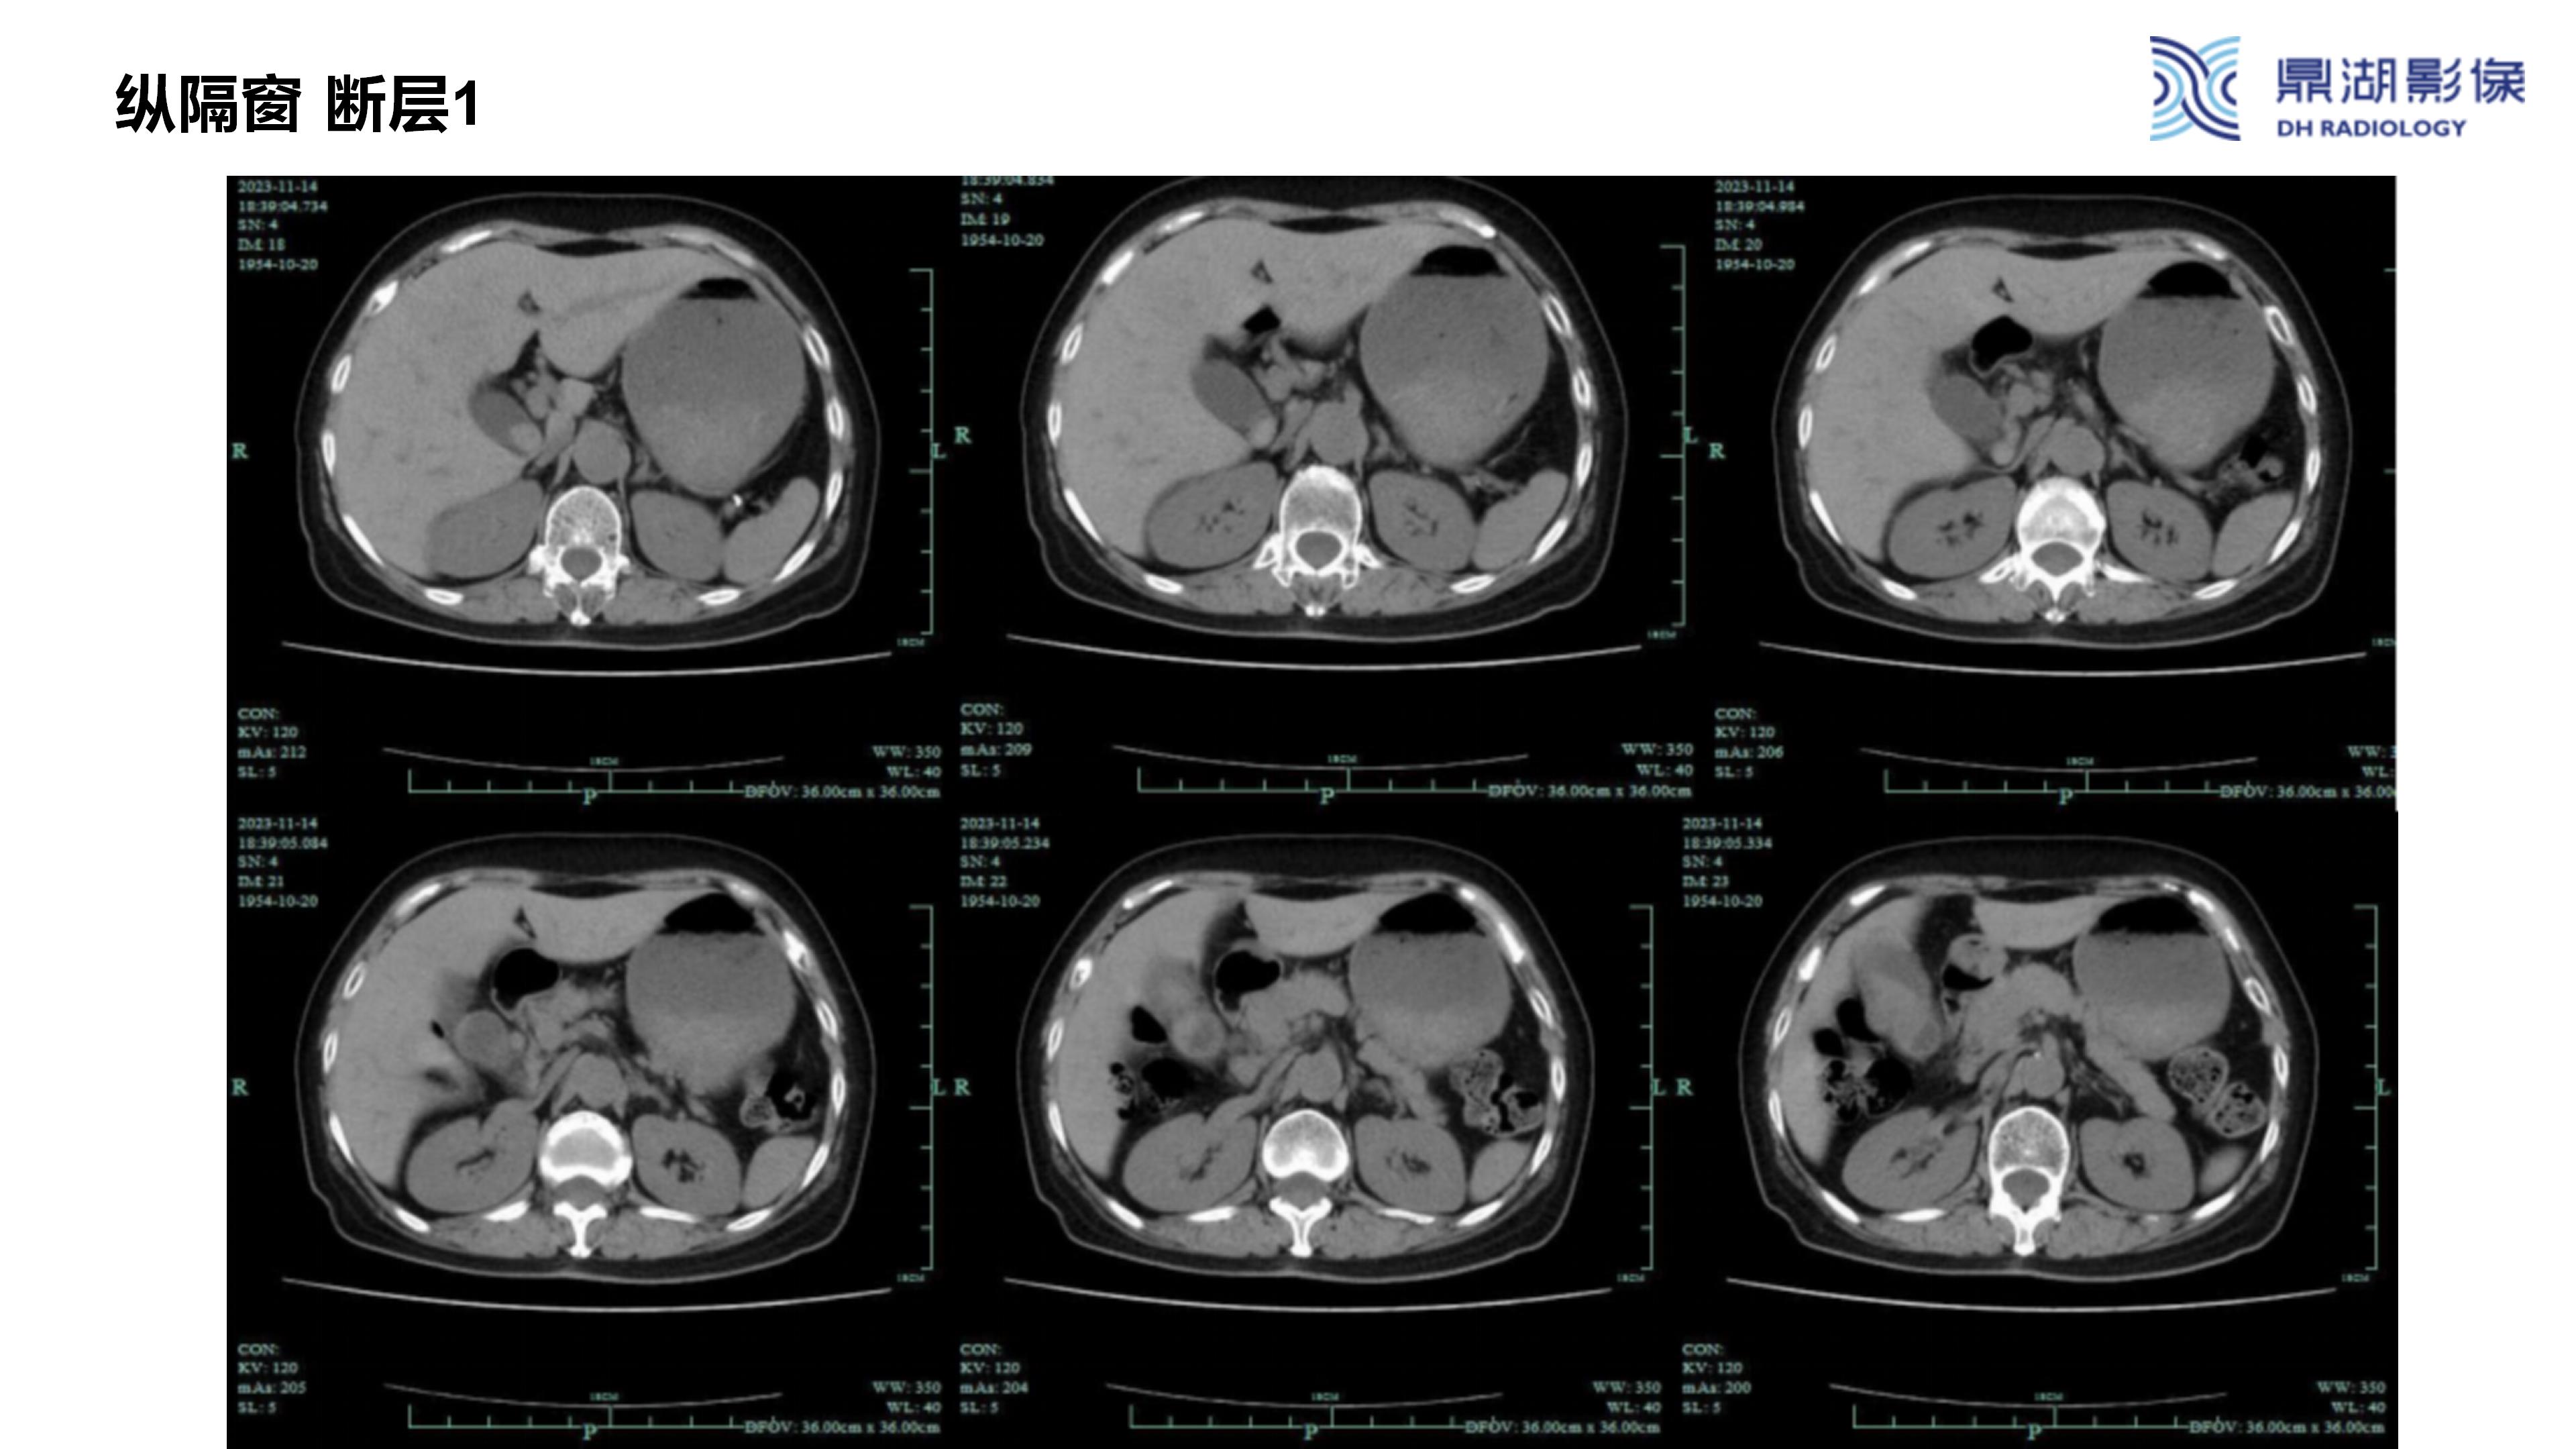

胆囊癌-鼎湖社群读片病例